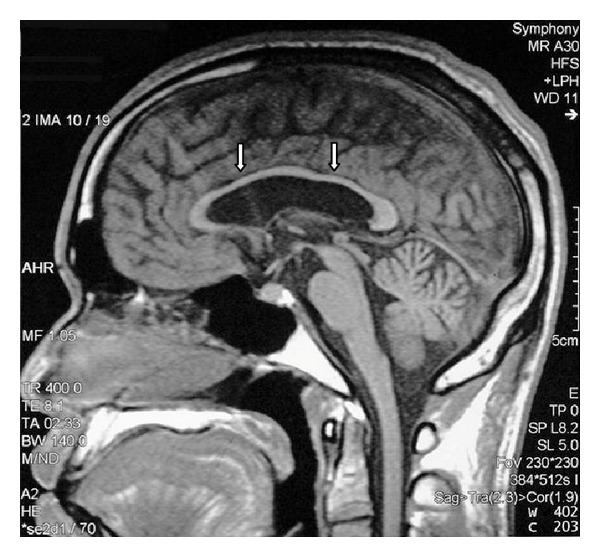

A 29-year-old male petrol station pump attendant was admitted with ataxia and clinical evidence of a sensorimotor polyneuropathy which developed over the preceding 3 months. He had cognitive dysfunction, hearing loss, and cerebellar clinical abnormalities that came on slowly over the three years. He had a fifteen-year history of sniffing mostly glue, occasionally paint thinners, and, in the recent two years, gasoline. Magnetic resonance brain imaging showed abnormalities of the cerebral cortex, cerebral white matter, corpus callosum, hippocampus, brainstem and cerebellar atrophy, hypointensities of basal ganglia, red nuclei, and substantia nigra as previously described in toluene sniffing. Abstinence for six months led to partial clinical improvement. Clinicians need to be aware of this preventable entity which has peculiar radiological findings which are being increasingly accepted as typical.

一名29岁的男性加油站油泵服务员因共济失调以及在前3个月内出现的感觉运动性多神经病的临床证据而入院。他有认知功能障碍、听力丧失和小脑临床异常,这些症状在3年里逐渐出现。他有15年的吸入史,主要是胶水,偶尔是油漆稀释剂,近两年来还吸入汽油。磁共振脑成像显示大脑皮质、脑白质、胼胝体、海马体、脑干和小脑萎缩,基底神经节、红核和黑质低信号,正如先前在甲苯吸入中所描述的那样。禁欲6个月导致临床症状部分改善。临床医生需要意识到这种可预防的疾病,它有独特的放射学表现,并且越来越被认为是典型的。